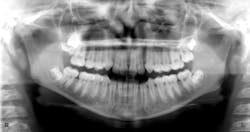

Healthy 11- (figure 1) and 14-year-old (figure 2) males present to the office for new-patient exams. Clinically, it was noted that the eruption patterns were not as they would typically be, primarily for the second molars in the 14-year-old. A panoramic radiograph was taken, revealing large radiopacities around the second molars on the right side. Both patients reported lack of pain upon palpation in these areas.